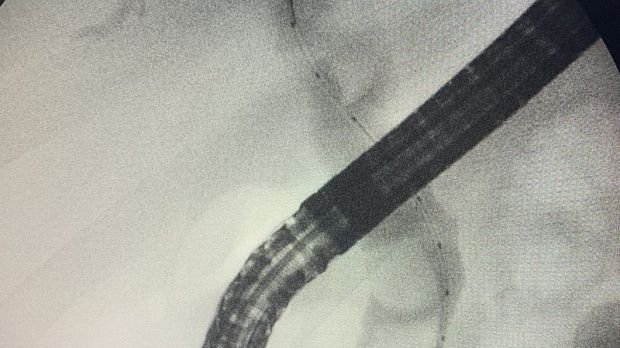

На следующий день произведена ретроградная холангиопанкреатография.

Отмечатся юкстапапиллярное расположение большого дуоденального сосочка тип-3. Канюляция папиллотомом pull-type ,контрастирование водорастворимым контрастом .

Рентгенологическая картина расширенния желчных протоков и наличие конкрментов в холедохе. Произведена эндоскопическая ограниченная папиллосфинктеротомия, отмечалось поступление темной желчи. Ревизия корзиной Дормия дали основания полагать ,что конкременты плотной консистенции.

Учитывая состояние пациента, большой степени вероятности осложнений и наличие крупных конкрементов в холедохе , принято решение следовать общепринятой тактике лечения при юкстапапиллярном расположении БДС - воздержаться от одноэтапного проведения операции с литэкстракцией. Произведено стентирование холедоха пластиковым стентом типа Pig-tail 10 Fr-130 мм, чем достигнуто адекватное дренирование желчных путей. Послеоперационный период протекал без осложнений. Биохимический анализ крови: билирубин общий-17.0 , билирубин прямой -13.0 , билирубин непрямой - 4, с-реактивный белок -24.3, скорость клубочковой фильтрации-37,4. По представленным результатам обследования в послеоперационом периоде, можно отметить положительную динамику в показателях пигментного обмена. Пациент в удовлетворительном состоянии выписан на амбулаторное лечение .